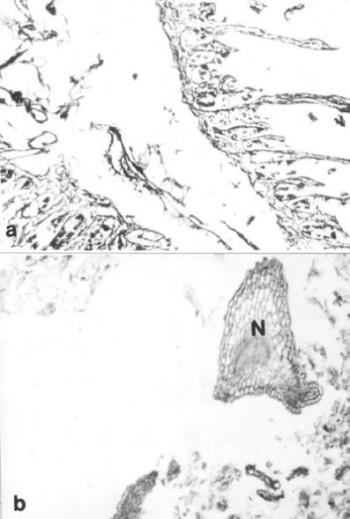

- Szövettani vizsgálatok múmia-szöveteken

- Hisztokémiai és immunhisztokémiai vizsgálatok